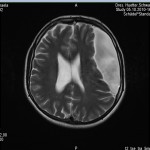

Ich stell euch hier noch eine kleine Galerie rein mit den neuesten Bildern. Ich denke es ist unübersehbar, dass das Ding gewachsen ist, außerdem mir meine komplette Hirnmittelline verschiebt und immer mehr Rücklagerung bekommt und Richtung Hirnsteuerungszentrum drückt. Meine häufiger auftretenden Stürze und Koordinationsprobleme werden also in naher Zukunft sicherlich nicht weniger werden und mein Doc und ich werden uns wohl auch zeitnah über eine weitere Klinik und eine mögliche weitere OP unterhalten müssen.

das ist bei mir ne Mischung aus Wasser und Gewebe. Das Thema ist, dass man die Flüssigkeit nicht einfach rausmachen kann, da sonst ein aktuer Unterdruck im Gehirn entsteht und das Gehirn reißen kann. Und dass ich dann nicht mehr all zu gut dabei aussehe denke ich erübrigt sich hier zu erwähnen….

Man hat in einer ersten OP damals schon mal einen halben Liter Flüssigkeit entzogen und dann gehofft, dass das gequetschte Gehirn sich wegen dem nachlassenden Gegendruck wieder weiter ausdehnt, aber das ist nicht passiert. Im Gegenzug hat die Zyste sich weiterhin wieder mit Wasser gefüllt und den entfernten halben Liter plus noch ein bisschen mehr wieder „nachgelegt“……